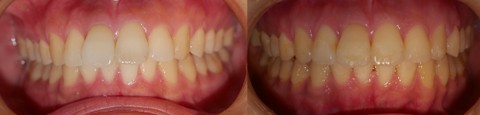

主訴:5月 の結婚式までに 10ヶ月 で出っ歯を治したい

結婚式の 5月 から逆算したうえで、余裕ある治療計画と審美的改善要素を意識しました。

間に合ってよかったと喜んでいただけて嬉しかったです。もしかすると、先生が一番喜んでいたのかも知れません。

審美面においては

・口ゴボの改善

・人中の短縮

・ガミースマイルの解消

・下顎と顔面正中の一致

・輪郭線の左右対称性

・額角(エラ)の減少

・輪郭の改善

・小顔化、下顔面高の短縮

・オトガイの梅干し状のシワの解消

・口角の左右対称

・口角が上がる笑顔

・ほうれい線の消退

などに配慮して治療しています